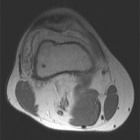

43 y/o male w 5 years of chronic R knee pain, worsening over the past 3 years. Feels like “crunching marbles”. Pain at night and worse with activity. No weight loss, fevers/chills. No systemic complaints.

PE: R knee effusion; crepitus, palpable masses near popliteal fossa, mild dec R knee ROM secondary to pain, neurovascularly intact, 5/5 motor.